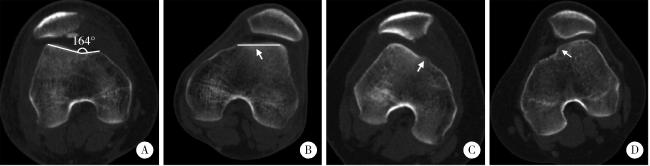

图2 基于轴位CT的Dejour分型示例

Figure 2 Examples of 4-grade Dejour classification based on axial CT

A, a 38-year-old male was diagnosed with Dejour A trochlear dysplasia, whose CT scan indicated a trochlear groove angle of >145 degree and symmetric trochlear facets; B, a 21-year-old male was diagnosed with Dejour B trochlear dysplasia, whose CT scan indicated a flat trochlea (arrow); C, a 16-year-old female was diagnosed with Dejour C trochlear dysplasia, whose CT scan indicated asymmetric trochlear facets and hypoplastic medial facet (arrow); D, a 17-year-old female was diagnosed with Dejour D trochlear dysplasia, whose CT scan indicated a positive cliff pattern (arrow). CT, computed tomography.

术前常规拍摄膝关节侧位X线片和电子计算机断层扫描(computed tomography, CT)。评估Dejour分型以反映滑车发育不良程度(图 2),测量髌骨高度(Insall-Salvati指数)与胫骨结节-股骨滑车沟(tibial tubercle-trochlear groove,TT-TG)间距[18](图 3)。术后1周内摄轴位CT,比较术前和术后的髌骨倾斜角、髌骨外移距离和等分偏移率(bisect offset ratio,BSO)比值[19](图 3),评估髌股关节对位关系改善情况。